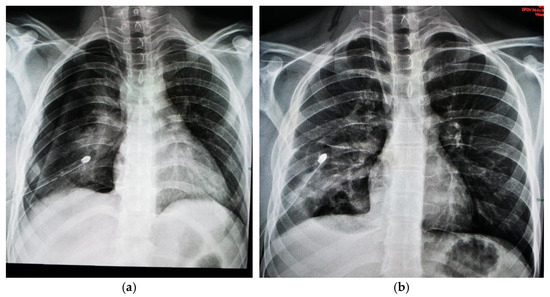

1.9.2. Case 2